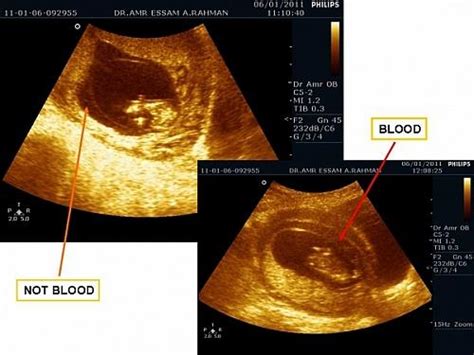

流产按照发展分为4个阶段.即先兆流产、难免流产、不全流产和完全流产。1、先兆流产出现少量的阴道出血,常为暗红色或血性白带,流血后可出现轻微下腹痛或腰部胀痛,但没有妊娠组织物排出。2、不全流产在先兆流产的基础上,阴道出血增多,腹痛加剧,继续发展下去,会发生部分胚胎组织排出官腔,部分嵌在宫颈口内,影响子宫收缩,导致大量出血、甚至休克,这种情况又称之为“不全流产”。“不全流产”,需要施行急诊刮宫术,清除阻塞于宫颈口的妊娠物,帮助子宫收缩,起到止血的作用。难免流产还包括了超声检查仅见空的妊娠囊,里面没有胚芽组织,或者胚芽组织没有原始心管搏动。3、完全流产发生腹痛、阴道出血后,怀孕的组织能全部自然排出体外,随后流血减少,腹痛减轻消失。在流产的4阶段中,只有处于先兆流产阶段才能进行保胎。不过作为孕妈妈,不用每天都被“流产”这朵愁云所笼罩,以积极乐观的心态享受美好孕程,相信一定可以顺利产下健康宝宝。

先兆流产指妊娠28周前,出现少量阴道道流血和(或)下腹疼痛,宫口未开,胎膜未破,妊娠物尙未排出,子宫大小与停经周数相符者;早期先兆流产是临床表现常为停经后有早孕反应,以后出现阴道少量流血,或时下时止,或淋漓不断,色红,持续数日或数周,无腹痛或有轻微下腹胀痛,腰痛及下腹坠胀感。 一般先兆流产的主要表现为怀孕后,阴道有少量出血,根据流血量和积聚在阴道内的时间的不同,颜色可为鲜红色、粉红色或深褐色。有时伴有轻微下腹痛,胎动有下坠感、腰酸腹胀。如果从民间传统的说法上讲,先兆流产的主要依据就是“见红”。